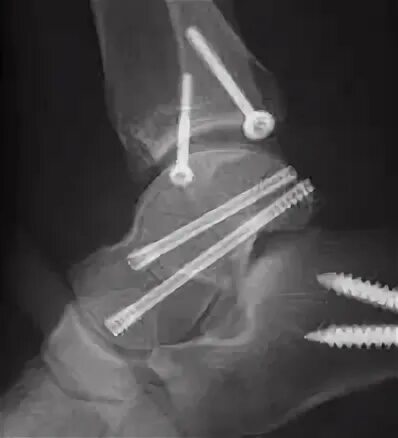

Остеосинтез мрт